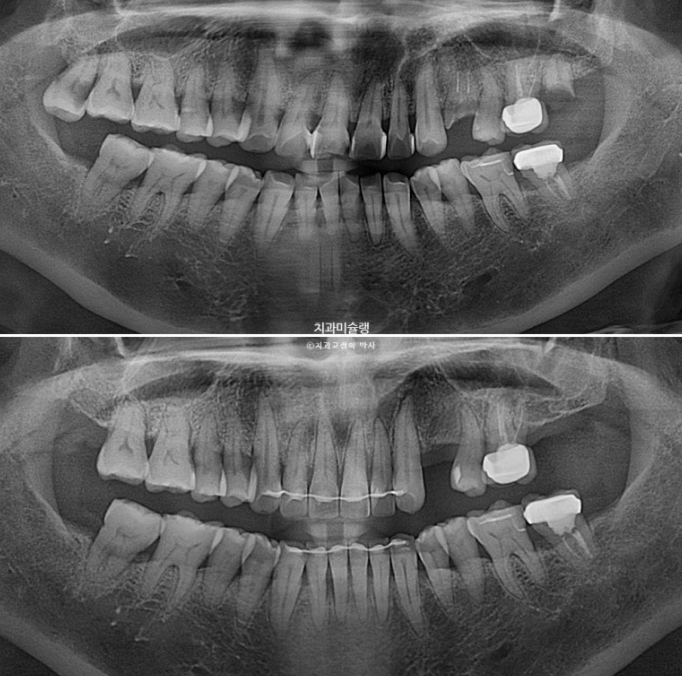

일년 반에 걸친 치료기간동안 치근흡수는 없고 치근평행도는 좋습니다.

아래 앞니는 치간삭제와 함입으로 위 앞니 사이사이 벌어진 공간을 이용하여 뻗친 각도와 골출을 개선하였으며

위 아래 앞니 각각 1.5-2mm 가량 뒤로 들어갔습니다.

임플란트 할 공간도 적절히 조절합니다.

충치로 인해 어금니들을 발치하게 되면서 교정치료를 병행하고자 오셨습니다.